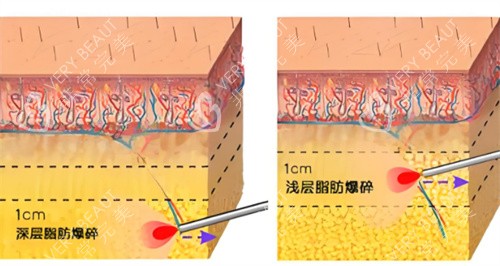

超声波碎脂:通过2.45GHz微波穿透脂肪层,使水分震荡产生60-70℃热能

探头设计:3mm浅层探头改善细纹,7mm深层探头提拉筋膜